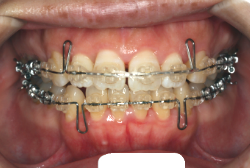

「ものがうまく噛めない」という主訴で来院したケースです。診断の結果、「骨格性反対咬合に伴う咬合不良+軽度叢生」と判明しました。原因としては特に下顎の左側が過成長したため、骨格性反対咬合になり、特に左側での噛み合わせが非常に悪くなっていると診断しました。初診時の写真を見ると、上下の正中線の大きなズレ、左側の噛み合わせの不良がはっきり分かります(黄色の矢印と緑の矢印は一致しているのが正しい状態です)。

そもそも、このような状態となっているのは骨の大きさに問題があるため生じていますので、場合によっては、「外科矯正」によって下顎の骨を外科的に縮めることで修正します。患者様が外科矯正をご希望されない場合は、従来ですと上下左右の小臼歯抜歯を行い矯正するのが普通です。

今回の患者様の場合は、「外科」も「小臼歯抜歯」も拒否されましたので、歯科矯正用アンカースクリュー(以下 アンカースクリュー)を用いて、下顎の歯列全体を後方に下げるという方法を取りました。

治療中の写真で、アンカースクリューより歯を後ろへ牽引しているのがお分かりいただけるかと思います。牽引を1年ほど続け、途中補助的に上下にゴムをかける(これを顎間ゴムと言います)手法なども追加し、全体で21ヶ月で治療を終えることが出来ました。

結局歯の本数を減らすことなく、すべてご自分の歯を残して、正しい配列と噛み合わせにすることができました。凸凹があまりひどくないため、簡単そうに見えると思いますが、このケースの初診の状態を見ると、熟練の矯正歯科医でも悩みのつきないケースです。まして、外科も出来ない、抜歯もイヤ、と言うことになると、従来の方法では治療不可能と考えられるのですが、アンカースクリューを使うことで最近は不可能が可能となってきました。